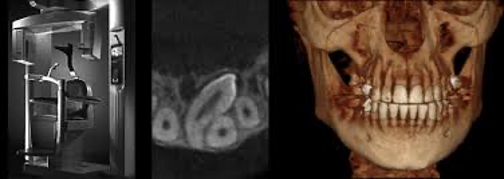

Orthophos XG 3D für zwei- und drei-dimensionale Röntgenaufnahmen von Sirona Dentsply bei Medicus Dental am Schaffhauserplatz in Zürich

Volumentomographie (DVT)

Die digitale Volumentomographie (DVT) ist ein dreidimensionales bildgebendes Verfahren und ist in der Mund- und Kieferchirurgie sehr oft notwendig, um das vorhersagbare therapeutische Ergebnis, zur Beispiel bei Implantationen, deutlich zu verbessern. 3D-Aufnahmen können auch bei Wurzelbehandlungen angewendet werden, wenn die Wurzelkanäle atypische und/oder sehr komplexe anatomische Strukturen aufweisen.